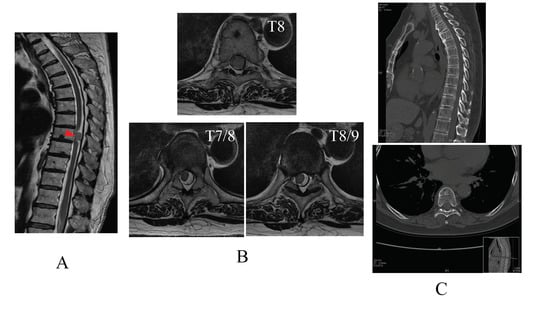

A 70-year-old woman had been increasingly facing walking difficulties for approximately 3 months. When her walking impairment started, she experienced several physical problems, including flank pain, balance impairment, sensory deficits, and muscle weakness (manual muscle testing grading system 3) under the umbilical region. She was diagnosed with intradural extramedullary spinal cord meningioma, which was observed in the thoracic spine region (T8) using T2-weighted magnetic resonance imaging and computed tomography images (Figure 1A–C). Surgical management of the tumor was planned. The day before the surgery, a physiotherapist evaluated the patient’s neurological impairment and disability. The patient could perform only mild voluntary movements in both lower limbs; showed sensory disorders, including hypesthesia of the hip, anus, and lower limbs; and required assistance for activities such as standing and walking, indicating severe impairment of activities of daily living.

Figure 1.

Mid-sagittal T2-weighted (T2WI) magnetic resonance image (MRI) of the thoracic spine region (T8, red arrow) (A) and coronal T2WI MRI scan, at the level of T7/8, T8, T8/9 (B). Sagittal and coronal computed tomography at the level of T8 (C). (D) Graph showing the chronological improvement in walking speed and step length in the 10 m walking test without the hybrid assistive limb (HAL) during the HAL gait sessions.